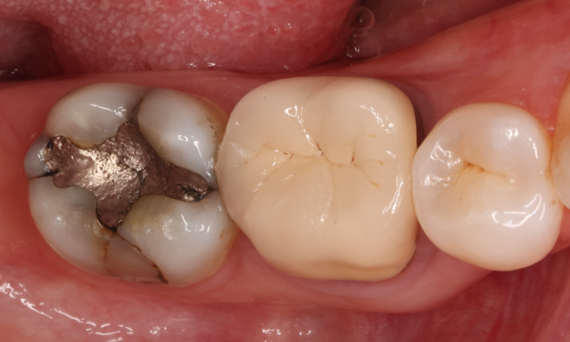

A lower second molar with sensitivity presented with cracks as well as an extensive Class I composite restoration on the buccal surface. According to the minimally invasive concept a CAD/CAM partial crown was planned, fabricated and bonded using CEREC Tessera in a single visit.

Before: Failed amalgam restoration needing replacement. Patient complaining of sensitivity and tooth presenting multiple cracks.

After: Chairside CAD/CAM partial crown restoration fabricated with CEREC Tessera Advanced Lithium-Disilicate glass ceramic.